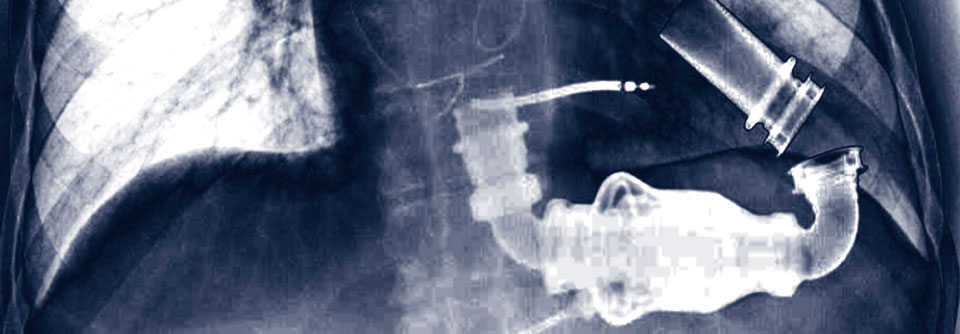

Diese Thoraxaufnahme zeigt das implantierte LVAD einer 65-jährigen Patientin mit Herzinsuffizienz. Diese Thoraxaufnahme zeigt das implantierte LVAD einer 65-jährigen Patientin mit Herzinsuffizienz. © Science Photo Library/Zephyr

In erster Linie kommen zur Kammerunterstützung linksventrikuläre Systeme (left ventricular assist device, LVAD) zum Einsatz. Etwa 900 dieser Geräte werden pro Jahr in Deutschland implantiert und halten bis zu zehn Jahre, berichtete PD Dr. Gloria Färber von der Klinik für Herz- und Thoraxchirurgie am Universitätsklinikum Jena. LVAD bringen einen erheblichen Gewinn an Lebenszeit gegenüber einer konservativen Therapie. Hinsichtlich des Zwei-Jahres-Überlebens stehen sie den Erwartungen nach einer Transplantation kaum nach (70 % bzw. ca. 75 %).

Ein LVAD wird in Parallelschaltung zum vorhandenen Organ an der Spitze angeschlossen und befördert das Blut vom…